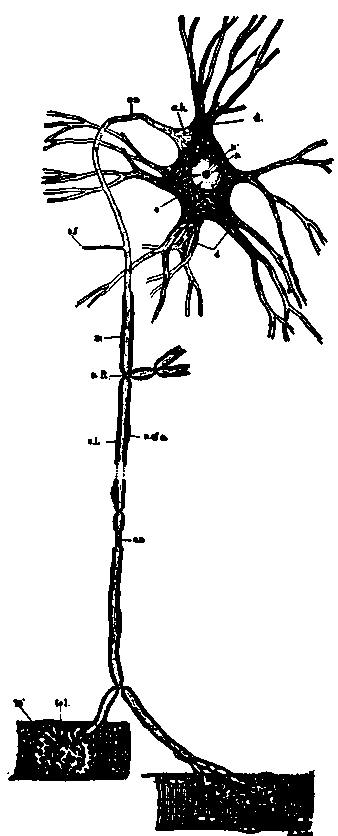

| 8. | Scheme of lower motor neuron | 114 |

| 22. | Motor cell of ventral horn of spinal cord from the human fetus | 133 |